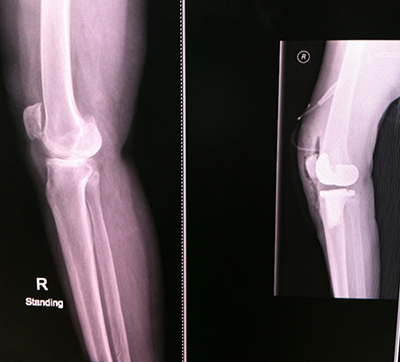

พอไปถึงก็จับเอ็กซ์เรย์ เพื่อรอแผ่นฟิล์มให้คุณหมอตรวจดู อาการเข่าเสื่อมของแม่ ก็พบว่าข้างขวาเสื่อมแน่ ๆ ส่วนข้างซ้าย ก็มีอาการเสื่อมแต่น้อยกว่า ตัดสินใจผ่าทีเดียวทั้งสองข้าง การผ่าตัดมีทั้งเปลี่ยนเฉพาะบางส่วน และเปลี่ยนเต็มข้อ สำหรับของแม่จัดเต็มข้อทั้งสองข้างเลยทีเดียว

ฟิล์มเอ็กซเรย์ก่อน (ภาพซ้าย) และหลัง (ภาพขวา) ของการผ่าตัดข้อเข่าเทียม ส่วนก้อนสีขาว ๆ ของภาพทางขวามือ คือข้อเข่าเทียมที่ใส่เข้าไป